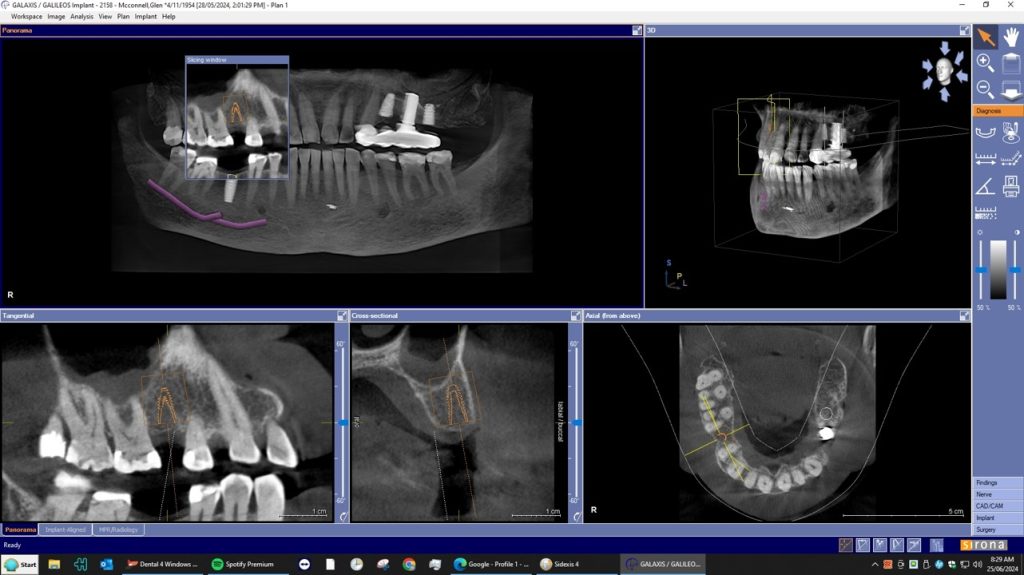

A dental Implant is a titanium “root” that integrates directly with the surrounding bone and replaces the function of the natural tooth. Neoss Implants are made using the best quality medical grade titanium, which is well known for its proven biocompatibility, and have a treated surface to facilitate bone integration.

The aim is to improve your health, chewing function and/or aesthetic appearance and once healing and restoration is complete you will be able to enjoy a wide variety of foods again.